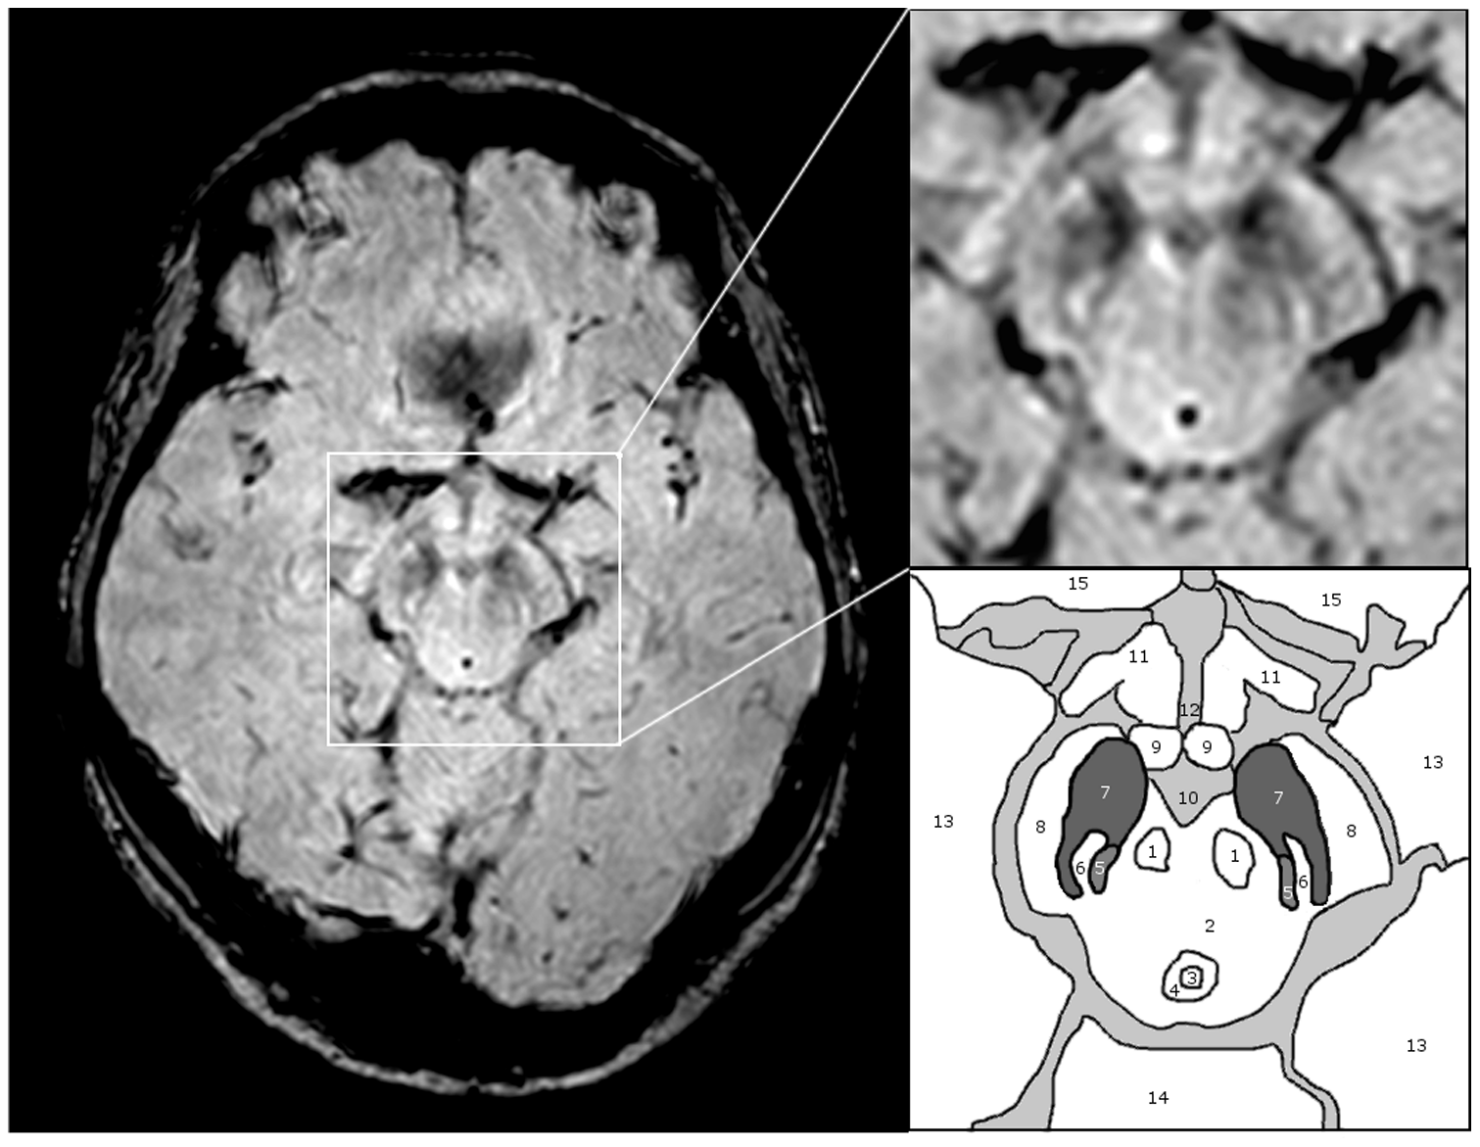

Příčinou byl nádor hypofýzy – žlázy umístěné na spodině mozku, která řídí produkci růstového hormonu.

Nádor způsobil nadprodukci růstového hormonu a vedl ke stavu zvanému akromegalie. U dospělých se růst obvykle projeví zvětšováním končetin, obličeje a měkkých tkání. V Rainerově případě však zřejmě došlo k pokračujícímu růstu kostí ještě po období, kdy by se růstové ploténky měly uzavřít. Jeho tělo se ocitlo v hormonálním chaosu.